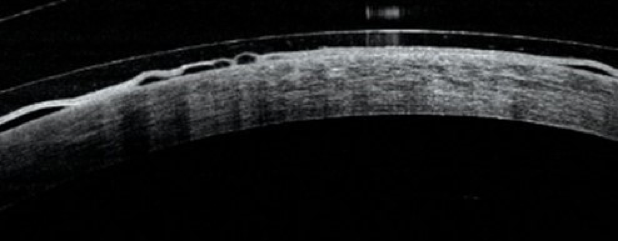

Finalmente, para mantener la superficie ocular en homeostasis y reducir los riesgos de rechazo, los autores recomiendan proporcionar suficiente oxígeno a la córnea y evitar el edema corneal central. Un lente escleral no debe tener más de 250 μm de grosor, debe estar fabricado con el material de mayor Dk disponible, idealmente superior a 150 y debe ajustarse de manera que la bóveda no sea superior a 200 µm. En otros escenarios clínicos, se debe considerar la inclusión de fenestraciones o surcos para incrementar la oxigenación. Esta información puede ser de gran utilidad para los pacientes con trasplante de córnea que requieren adaptación de lentes de contacto. Ver Figura 2.

Figura 2. Bullas epiteliales relacionadas con lentes de contacto esclerales y trasplante corneal. Messer, Fosso, & Kuzniar (2023).